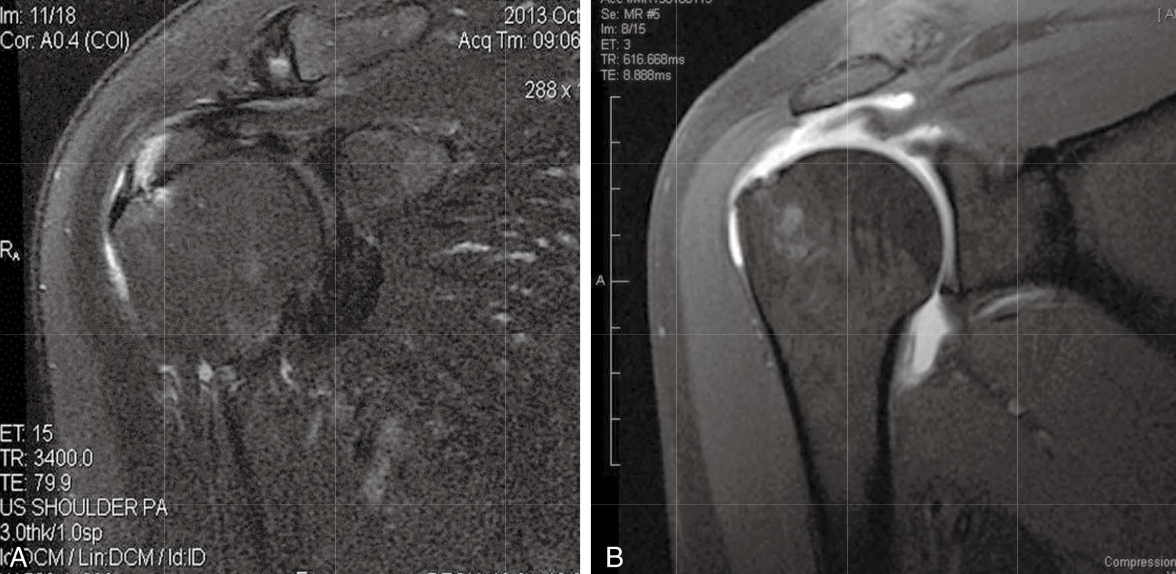

Первичный импиджмент синдром — боль и воспаление в субакромиальном пространстве в результате сдавливания ротаторной манжеты нижней поверхности акромиона, клювовидно-акромиальной связки и нижней поверхности акромиально-ключичного сустава.

Вторичный импиджмент синдром — боль и воспаление в области вращательной манжете и субакромиальном пространстве из-за невозможности удерживать головку плечевой кости в центральном положении, что приводит к изменению механики плечевой кости и компрессии вращательной манжеты. Обычно это наблюдается у молодых пациентов, у которых может быть слабость или нестабильность плечевого сустава и часто плохой контроль над лопаткой. Это также может быть связано со слабостью вращательной манжеты плеча.

Внутренний импиджмент — повторяющийся контакт большого бугорка и суставной поверхности задней части ротаторной манжеты с задне-верхним гленоидом в отведенном, ротированном наружу положении. Это обычно наблюдается у спортсменов метателей и может привести к частичным разрывам суставной вращательной манжеты и разрывам задне-верхней суставной губы. Это может быть связано с незначительной нестабильностью плечевого сустава, уплотнением задней капсулы, а также с нарушением внутренней ротации плеча, дискинезией лопатки.